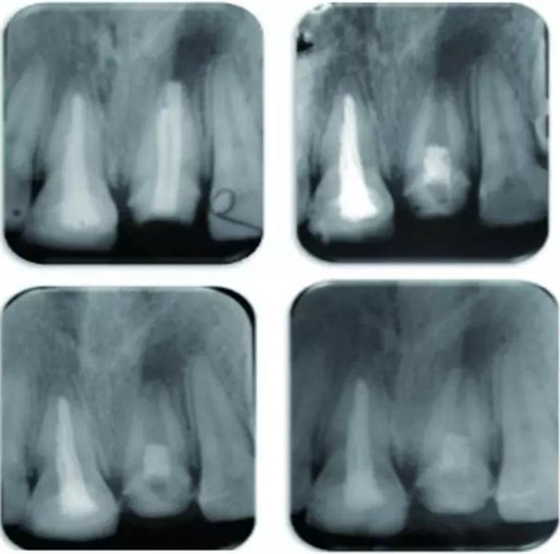

圖 21治療全過程,圖A 為治療前根尖片,圖B 為術(shù)后根尖片,圖C 顯示治療7 個(gè)月后根尖陰影縮小,圖D顯示治療后13個(gè)月根管口變窄

結(jié)果為,兩患牙分別在隨訪13個(gè)月及14個(gè)月時(shí)表現(xiàn)出根尖周炎的臨床恢復(fù)體征和/或癥狀。21患牙顯示出根管變窄以及根尖部硬組織沉積而形成根尖封閉。

例為兩名年齡分別為26歲和12歲的男性患者,各有一顆恒牙(牙位分別為21與35)因患有根管治療后持續(xù)性根尖周炎而需進(jìn)行再治療。用Carvene 牙膠溶解劑和ProTaper普通旋轉(zhuǎn)式再治療根管銼去除患牙根管內(nèi)充填的牙膠,接著進(jìn)一步用旋轉(zhuǎn)再治療銼和大量次氯酸鈉對根管進(jìn)行化學(xué)機(jī)械法清理,然后用Metapaste 干燥根管。對21和35兩患牙進(jìn)行牙髓再生術(shù)治療。將根尖周的出血引入消毒后的根管內(nèi),用礦物三氧化物聚合物(MTA)填料覆蓋血塊,根管口修復(fù)材料填充。